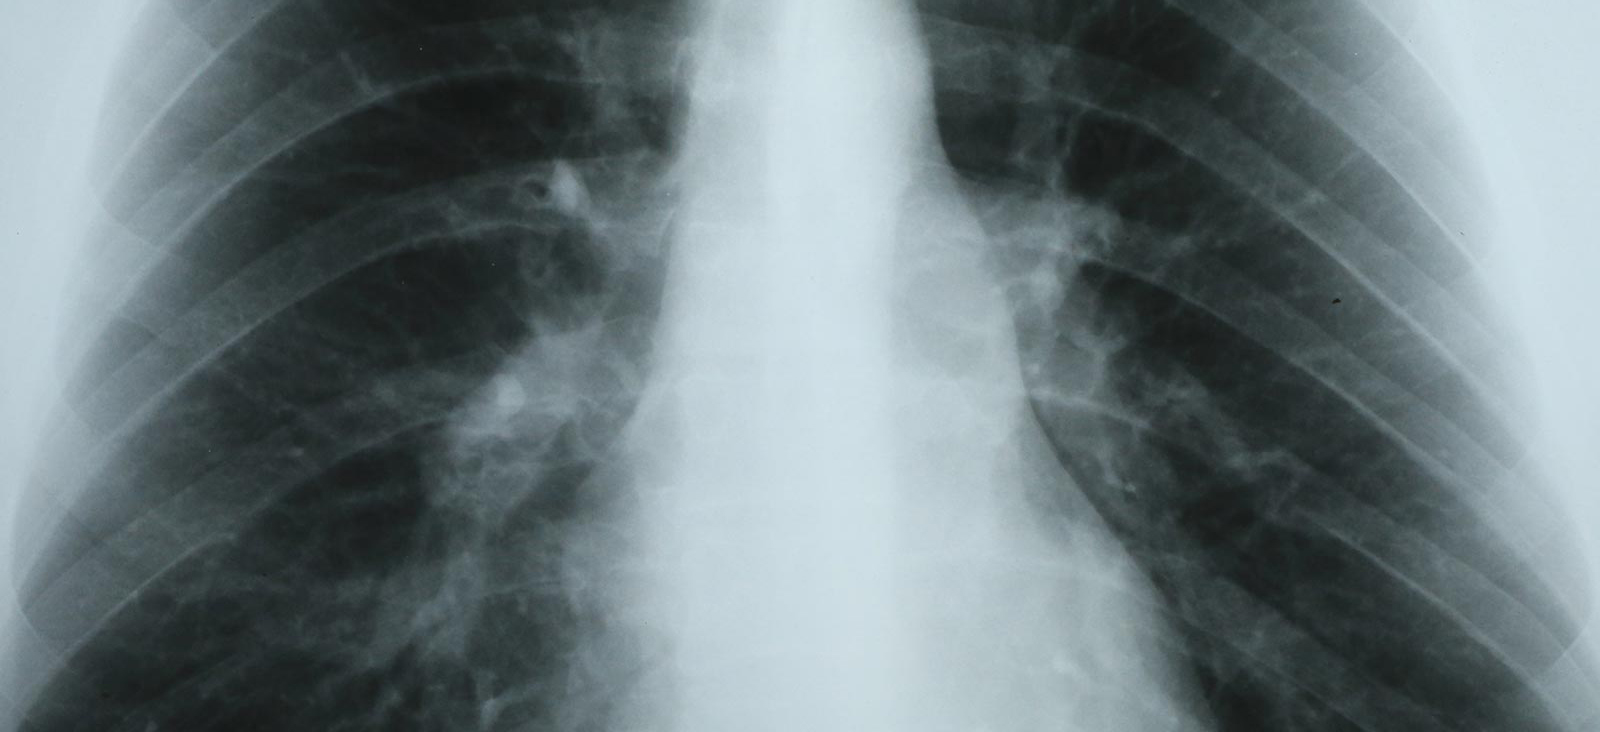

Thoracic Surgery

at UT Southwestern Harold C. Simmons Comprehensive Cancer Center at Moncrief Cancer Institute